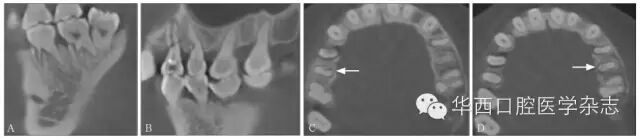

3.3.2 与牙内吸收鉴别根折裂轴位可见颊舌向贯通的折线,根管壁不连续;内吸收则是根管内径的局部扩大,根管壁连续性未中断(图9)。

ABCBCT矢状位、冠状位见15牙根折裂,冠状位见根管壁较对侧同名牙变薄,折片向颊侧移位,C:轴位见15牙颊侧根管内径扩大,提示有内吸收。

9 内吸收导致根折裂